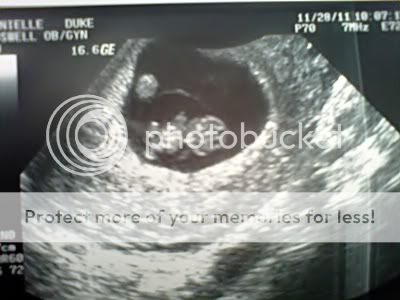

We had a Dr.'s appt today and everything went fantastic. I am completely in love and so happy. Baby was being stubborn (just like mommy and daddy) and wasn't in the best position for a good measurement, again, but the Dr. said s/he is measuring right around 9 ish weeks, when it should be. She said everything look amazing and she was very pleased with all the progress.

Here's to bragging on our LO and how cute our little stinker is.